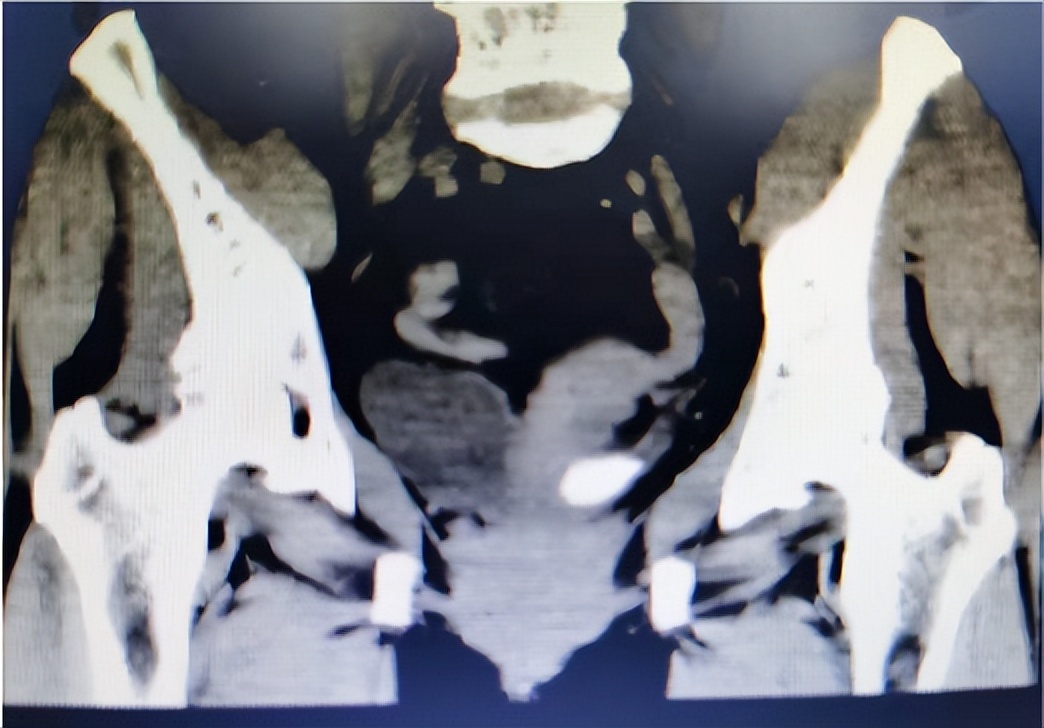

根据王阿姨的描述,我首先怀疑是尿路结石。于是,给王阿姨做了常规腹部检查,结果发现,双侧肾区未见明显异常的包块与隆起,左侧肾区叩击痛明显。随后的门诊CT结果显示,左侧输尿管结石,左侧肾盂积水并感染。看到CT结果后,我以输尿管结石收住入院。

安排王阿姨住院后,对其进行了全面的检查,检查发现患者左肾筋膜增厚,双肾见多发小囊状密度减低影,最大直径约13mm,左侧肾中极水平背阔肌内见梭形脂肪密度影,密度欠均匀,左侧髂腰肌见斑片状密度减低影,主动脉及双侧髂动脉见点状高密度影。提示患者还除左侧输尿管膀胱入口处有结石,左肾积水合并感染外,还存在双肾囊肿、左侧腰背中部背阔肌脂肪癌、腰椎退行性改变,主动脉及双侧络动脉硬化。

对王阿姨的情况进行评估后,决定先解决患者的结石情况。因此,在完善术前检查和征得患者同意后,与入院第四天行输尿管镜下激光碎石D-J管内置引流术治疗。术前从CT片观察,考虑有部分结石位于输尿管,另外一部分位于膀胱内,但是手术中发现结石全部是位于输尿管内的,结石比较大直径达到2.5cm,属于比较少见的输尿管结石。这可能是结石长期处于输尿管壁段,逐渐增大,造成了输尿管末端扩张凸向膀胱而引起的。